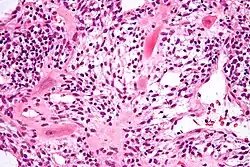

Histomorphology

- Implantation site intermediate trophoblast[1]

- pleomorphic irregular nuclei, large and hyperchromatic, may show multinucleation

- abundant eosinophilic to amphophilic cytoplasm

- infiltrative growth (splitting muscle, replacing vascular wall ...etc)